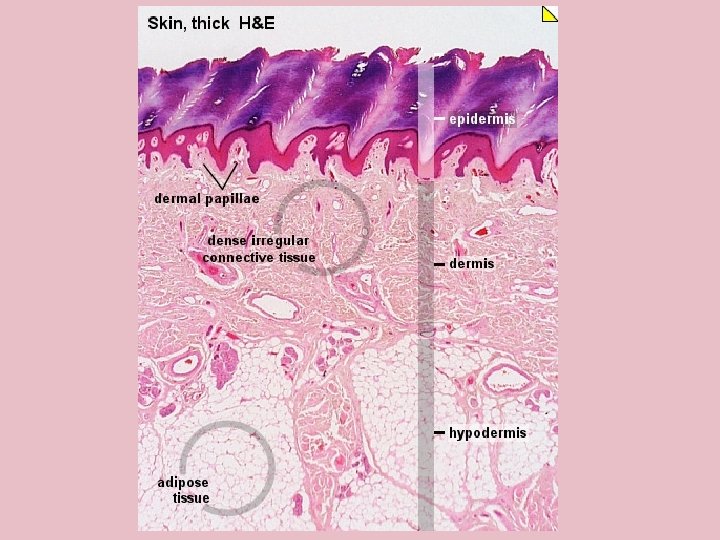

TYPES OF SKIN • Thin skin – covers all parts of the body except for the palms and palmar surfaces of the digits and toes. – lacks epidermal ridges – has a sparser distribution of sensory receptors than thick skin. • Thick skin (0. 6 to 4. 5 mm) – covers the palms, palmar surfaces of the digits, and soles – features a stratum lucidum and thick epidermal ridges – lacks hair follicles, arrector pili muscles, and sebaceous glands, and has more sweat glands than thin skin.

Specific Layer of the Skin Epidermis: • Composed of keratinized stratified squamous epithelium Dermis: • Papillary region composed of areolar tissue • Reticular region composed of dense irregular connective tissue Hypodermis: • Composed of areolar tissue with abundant adipocytes

Layers of the Dermis • Reticular region: consists of dense irregular CT Contain most of the accessory Structures 3. Papillary Region: Consist of areolar Tissue 4. Dermal Papilla: Fingerlike projections that greatly increase surface area 4 3 1 2